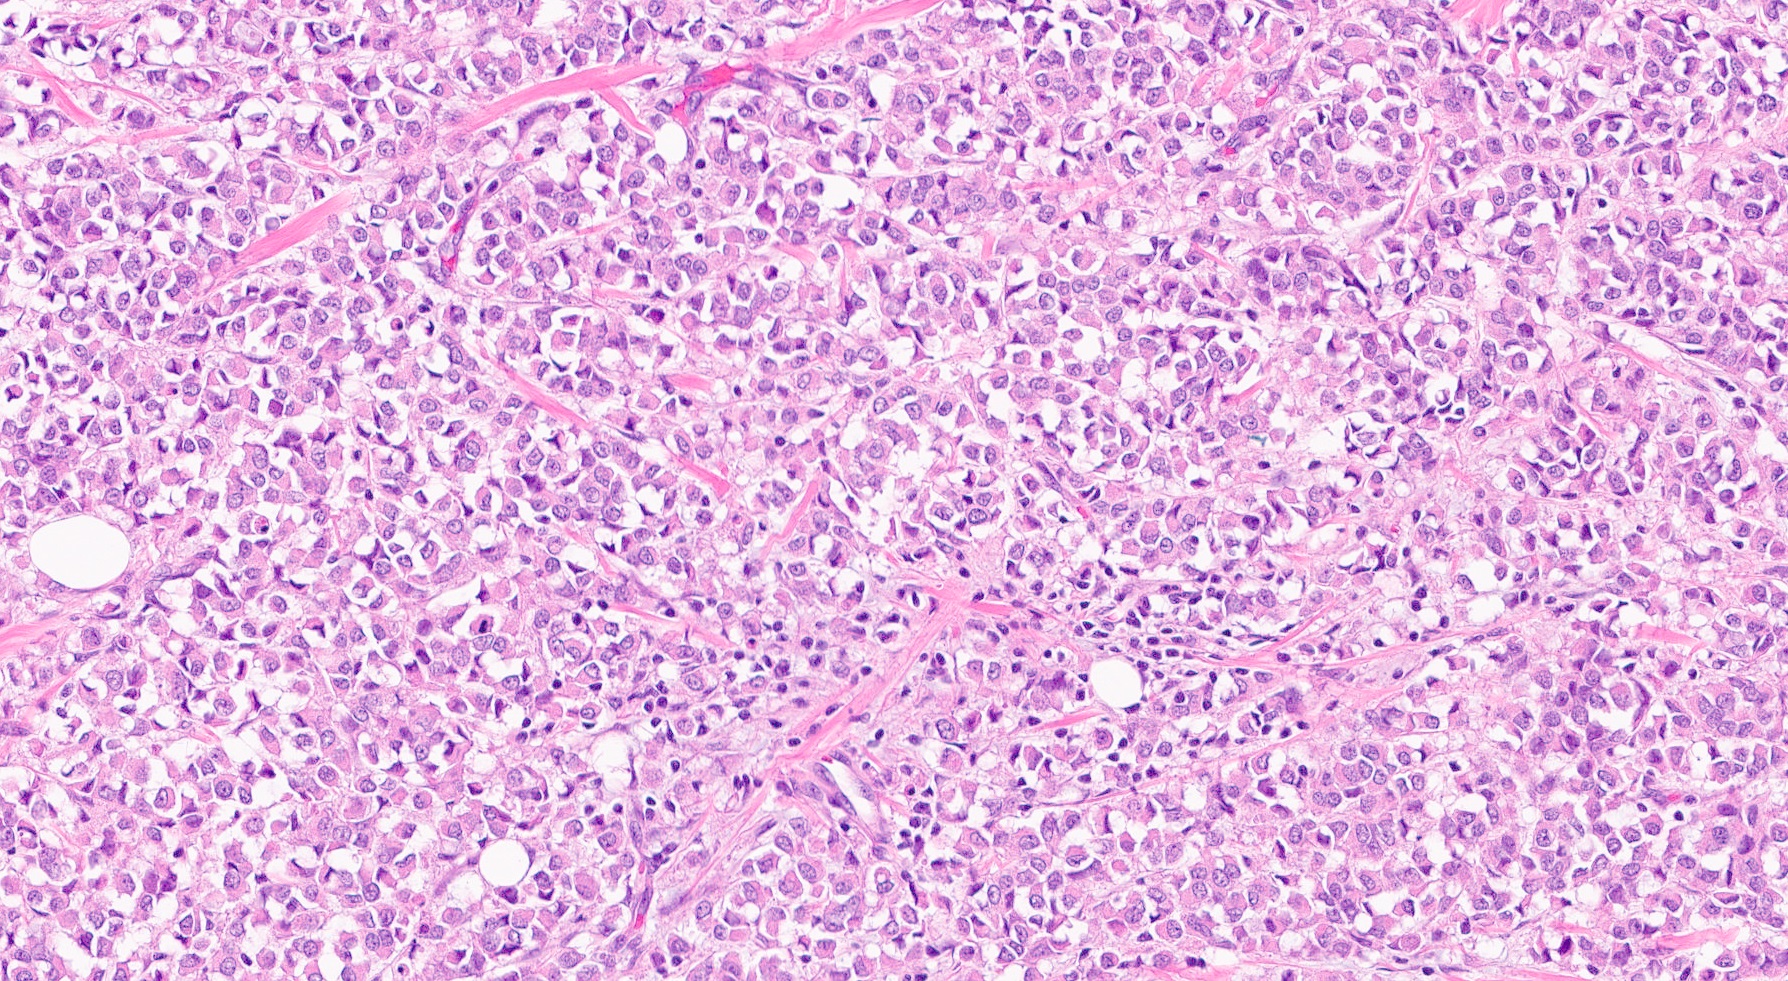

Microscopic (histologic) description

- Tumor cells arranged in single files, cords and single cells (Breast Cancer Res 2015;17:12)

- Can be arranged concentrically around normal ducts, giving a targetoid appearance

- Tumor cells discohesive, small, monomorphic and lacking marked atypia

- Round or notched ovoid nuclei, usually grade 1 or 2 nuclear score

- Scant cytoplasm, occasional with intracytoplasmic lumen

- Mitosis infrequent

- Desmoplastic reaction and necrosis uncommon

- Requires high index of suspicion for metastasis

- Single and scattered tumor cells with mild atypia requires examination on high power magnification with caution (Int J Surg Case Rep 2021;80:105612)

Microscopic (histologic) images